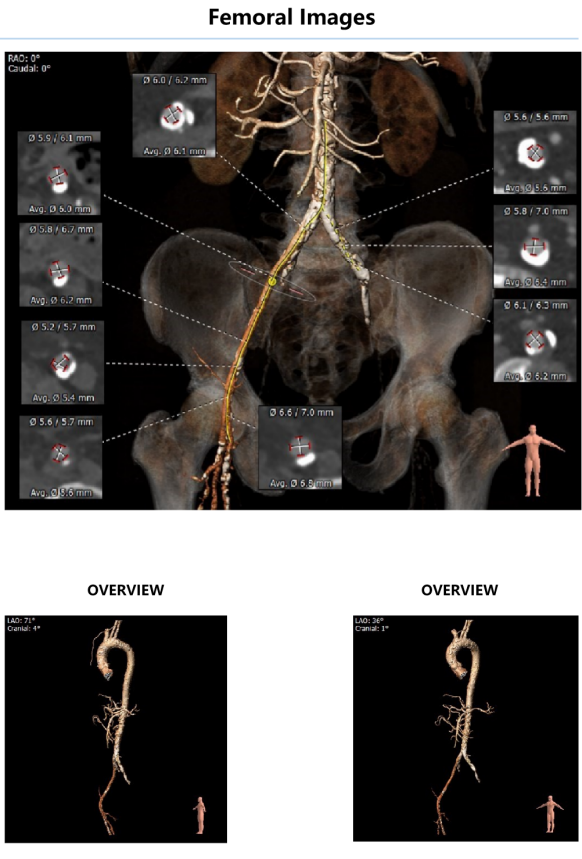

外周血管影像:

入路血管严重钙化,左髂外动脉次全闭塞病变,右髂动脉局部环状钙化,血管内径较细。

④患者腹主动脉及双侧髂股动脉多发重度钙化,左髂外动脉次全闭塞病变,右髂动脉局部环状钙化,血管内径较细,血管并发症风险较高,必要时可选择桡动脉及其他外周动脉作为入路血管。

右侧股动脉入路建立后,在双侧髂总动脉汇合处遭遇顽固钙化,器械无法向心推进,术中改以左侧腋动脉为主入路。

本例TAVR手术,既是我院开展的第一台TAVR手术,同时也是沛嘉Taurus瓣膜上市后第一次采取腋动脉入路的TAVR手术。患者基本情况较差,合并有高血压、糖尿病、冠状动脉性心脏病等疾病。既往有明确脑梗史,入院后颈部超声则提示右侧颈总动脉有效内径较小,脑部存在供血不足风险。经CT评估后确认,患者外周血管内壁普遍钙化严重,左侧髂外动脉存在钙化封堵,整体入路风险较大,左侧辅入路较难建立。经术前讨论,改以左锁骨下动脉为辅入路血管。术中造影示患者主动脉瓣严重钙化,并有中度反流影。在右侧主入路大鞘置入过程中,由于患者血管钙化迂曲情况复杂,大鞘难以进入。经内外科同仁商讨,改以左侧腋动脉切开入路为主入路。